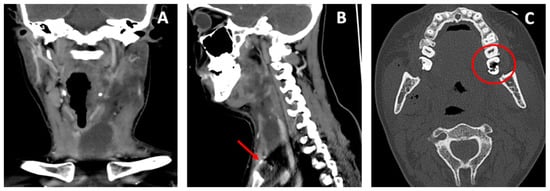

2. Case Report